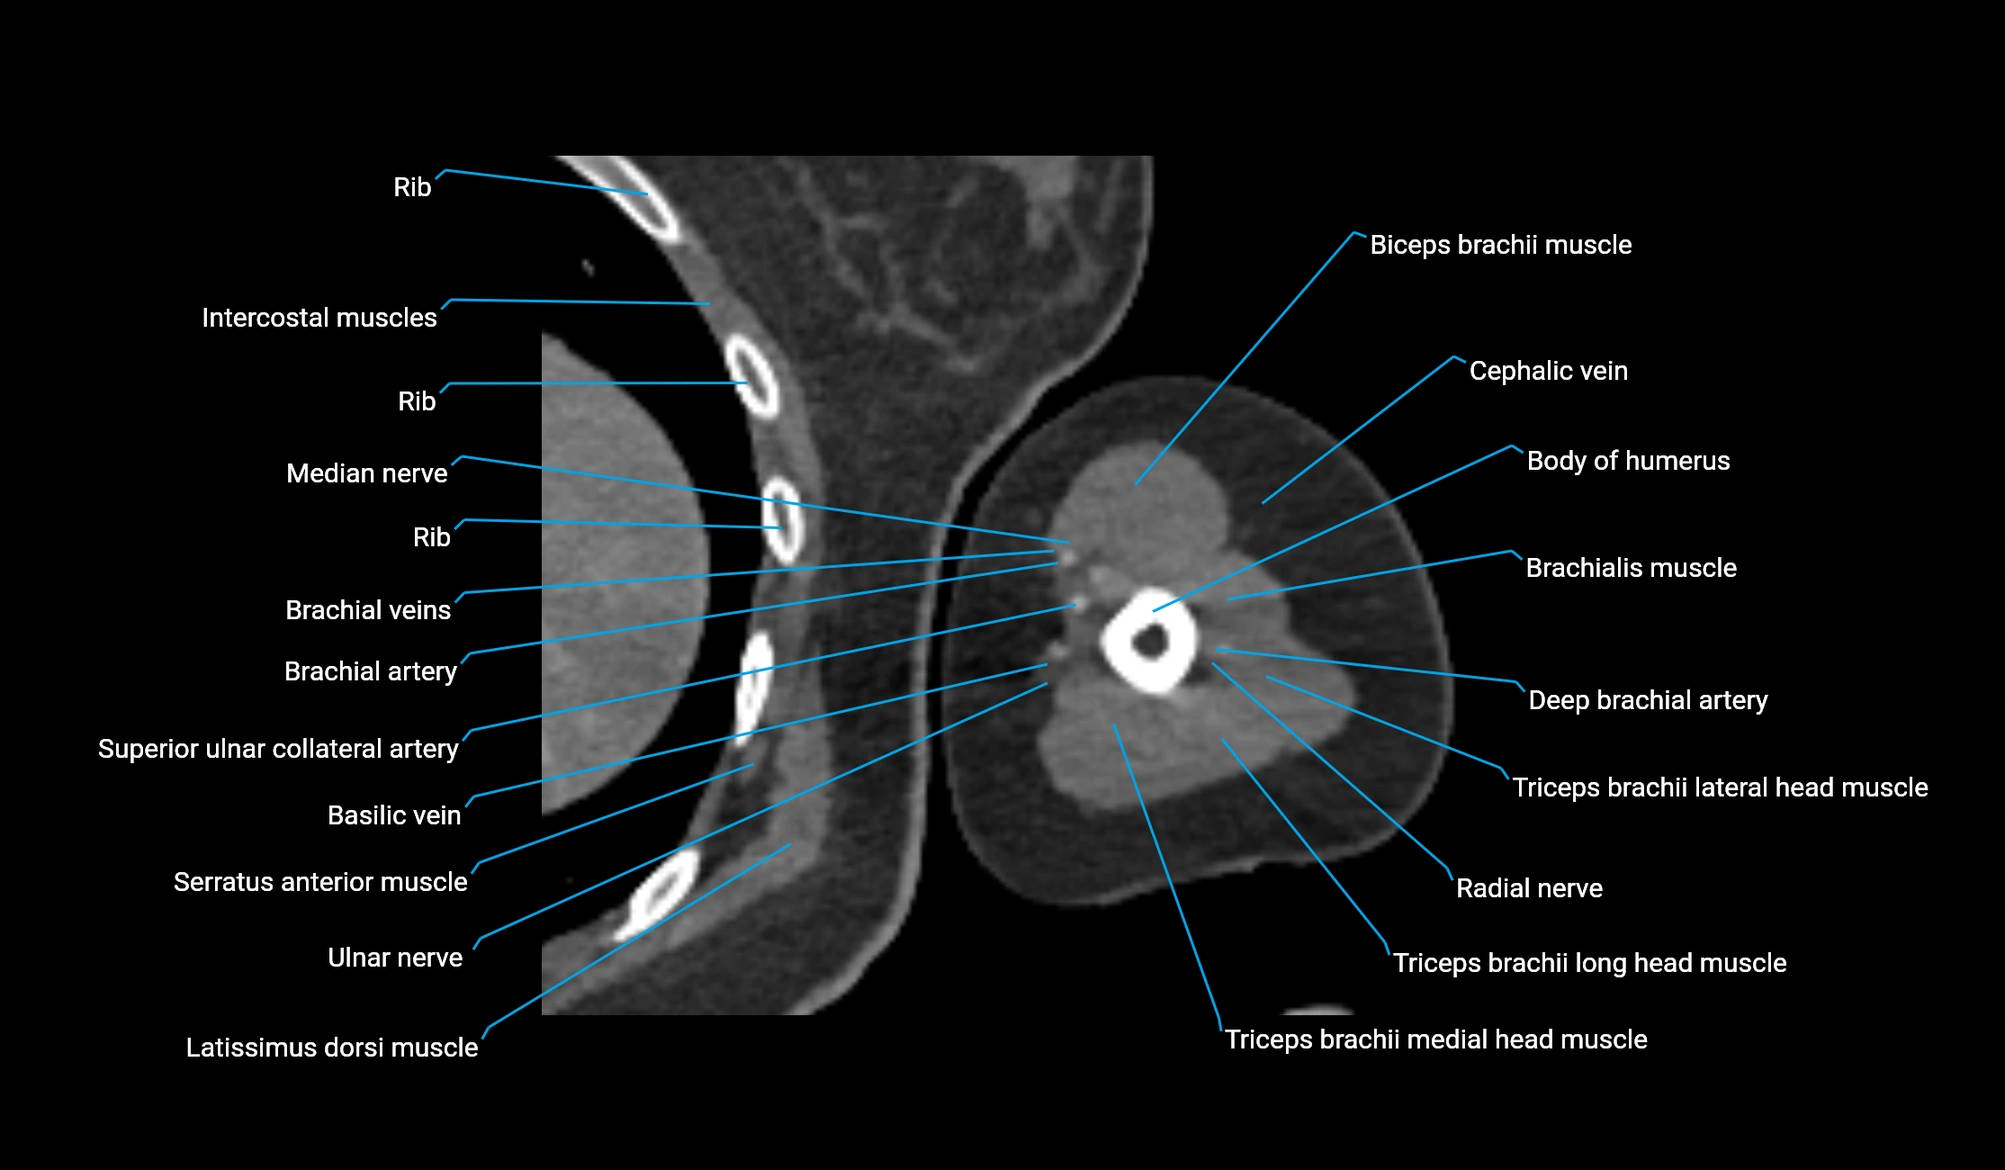

- Body of humerus

- Brachial artery

- Brachialis muscle

- Cephalic vein

- Deep brachial artery

- Long head of triceps brachii muscle

- Lateral head of triceps brachii muscle

- Medial head of triceps brachii muscle

- Median nerve

- Radial nerve

- Superior ulnar collateral artery

- Ulnar nerve

- Biceps brachii muscle